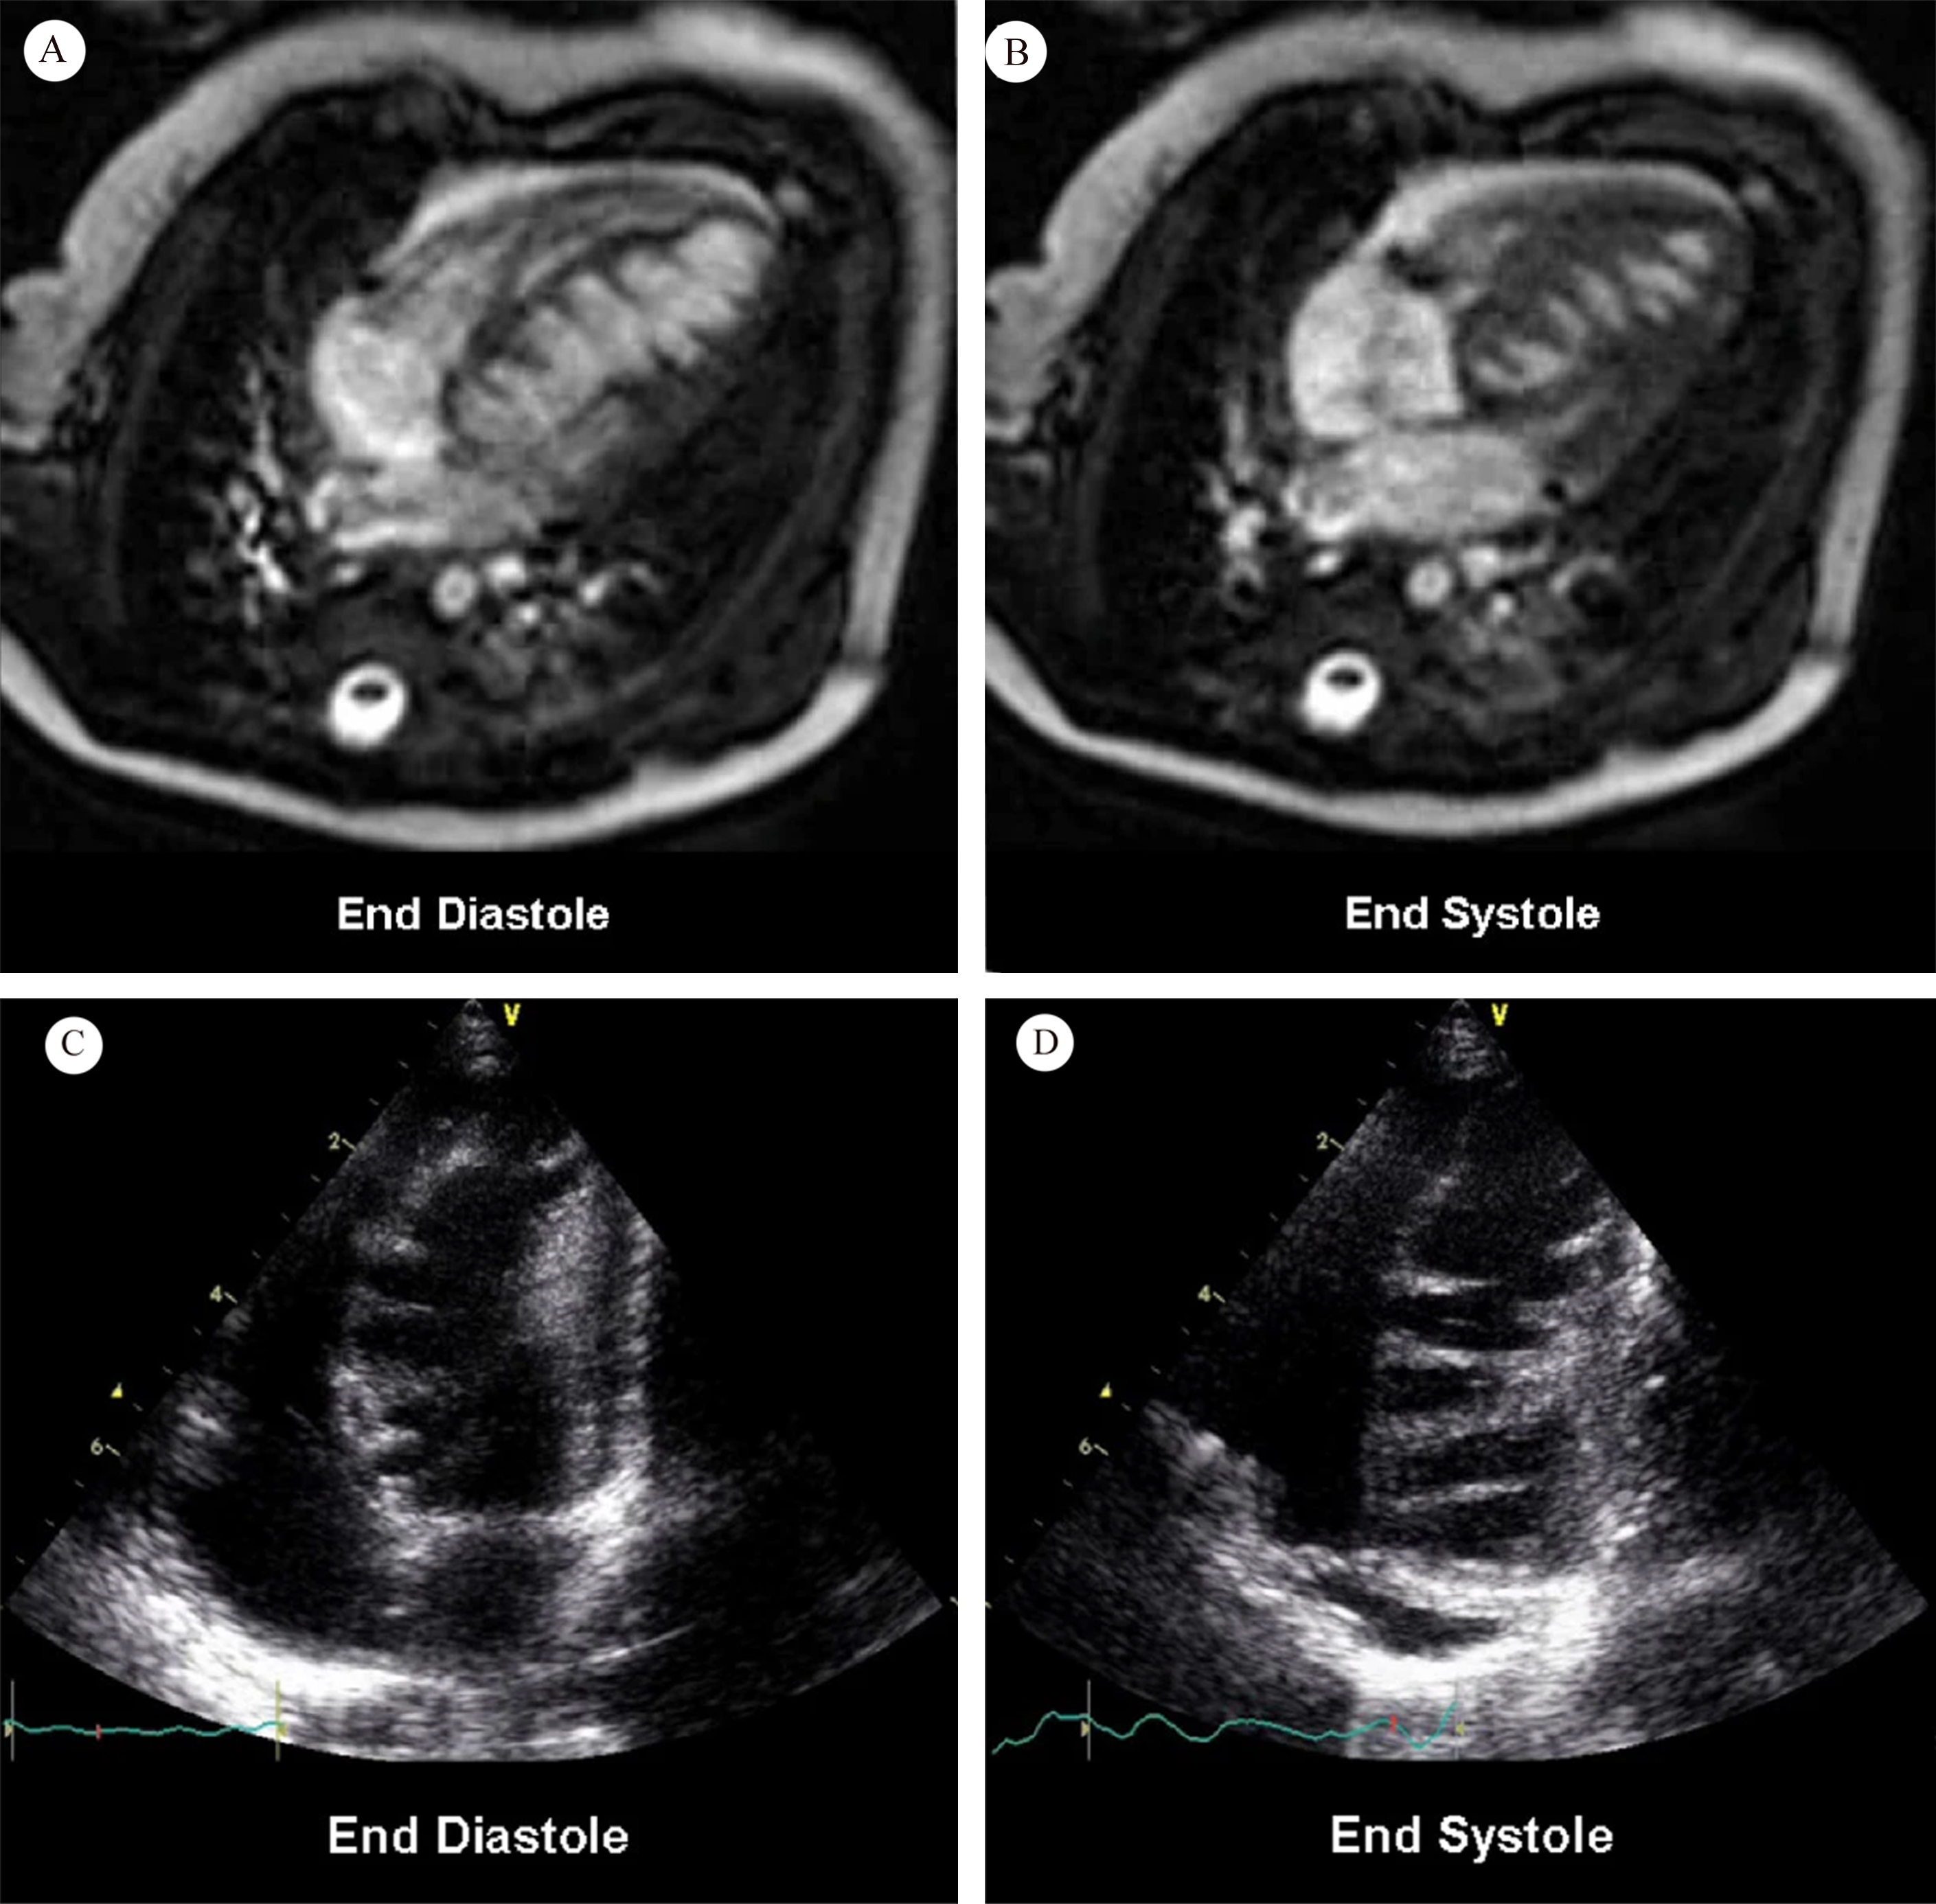

Saw-tooth cardiomyopathy (STC), first discovered in 2009 [1, 2], is a rare form of left ventricular cardiomyopathy, mainly affecting the apex and middle segment of the left ventricular wall and inferior wall. It may be evident in transthoracic echocardiography on admission. In most reported cases cardiac magnetic resonance (CMR) can provide a clearer view of the internal structure of the heart, with multiple dense myocardial protrusions similar to saw-tooth like crypts. These differ from left ventricular noncompaction (LVNC), which is characterized by noncompact myocardium in the layer of finely trabeculated myocardium adjacent to a layer of compacted myocardium [3]. The clinical course of STC ranges from asymptomatic to acute heart failure, and it can also be associated with a variety of cardiac complications. Typical images for STC are shown in Fig. 1 (Ref. [2]), and for LVNC in Fig. 2 (Ref. [3]) for comparison.

Fig. 2.Orange line = compacted myocardium; Blue line = noncompacted myocardium. Fig. 2A,B demonstrate long axis noncompaction ratio measurement, with a maximum ratio of 3.4. Fig. 2C,D demonstrate a short axis noncompaction ratio at diastole of 3.6, and a systole of 2.2, respectively (Fig. 2 is cited from Weir-McCall JR, et al. [3]).